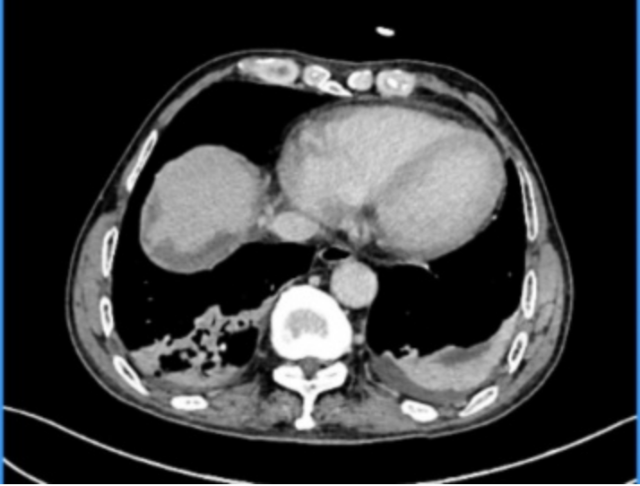

▲术后复查影像显示下腔静脉血流通畅、充盈良好

在多学科团队的紧密协作下,这台高风险、高难度手术最终取得圆满成功。患者术后转入ICU接受精心监护,生命体征平稳,顺利渡过了手术危险期。术后第4天增强CT检查显示下腔静脉管腔通畅、血流充盈良好,无狭窄及血栓形成。最终的病理学检查报告证实:肿瘤及癌栓均被完整切除,手术切缘阴性(R0切除),达到了根治性效果。令人欣喜的是,患者术后恢复顺利,术后第9天即康复出院。